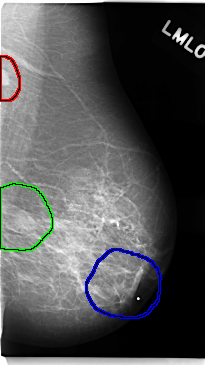

FILE: C_0146_1.LEFT_MLO.OVERLAY

TOTAL_ABNORMALITIES 3

ABNORMALITY 1

LESION_TYPE MASS SHAPE OVAL MARGINS CIRCUMSCRIBED

ASSESSMENT 5

SUBTLETY 5

PATHOLOGY MALIGNANT

TOTAL_OUTLINES 1

ABNORMALITY 2

LESION_TYPE MASS SHAPE LOBULATED MARGINS ILL_DEFINED

ASSESSMENT 4

SUBTLETY 4

ABNORMALITY 3

LESION_TYPE MASS SHAPE IRREGULAR MARGINS ILL_DEFINED

LEFT_MLO LINES 4736 PIXELS_PER_LINE 2656 BITS_PER_PIXEL 12 RESOLUTION 50 OVERLAY